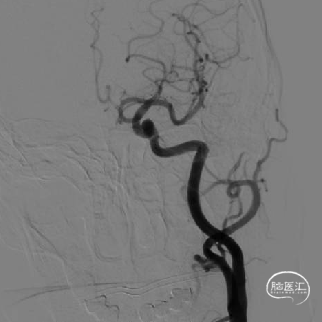

取平卧位,全身麻醉后行右侧股动脉穿刺,建立治疗通路。

Headway™微导管越过动脉瘤至M1。输送FRED 4513血流导向密网支架至于微导管末端平齐,回撤系统至颈内动脉末端。

经Headway™ 27微导管跨瘤颈释放FRED 4513血流导向密网支架,造影确认远端着陆点是否与预期一致。发现支架远端密网工作段未完全覆盖动脉瘤颈。

回收支架后,调整远端着陆点。使FRED®血流导向密网支架的末端无效段处于颈内动脉末段分叉处,再次造影后确认支架的密网工作段已覆盖整个动脉瘤颈。

确认远端打开良好后,完全释放支架。

术后即刻Vaso-CT显示支架贴壁良好。

术后即刻工作位造影提示,支架打开及贴壁良好,支架内血流通畅,瘤囊内造影剂滞留明显。